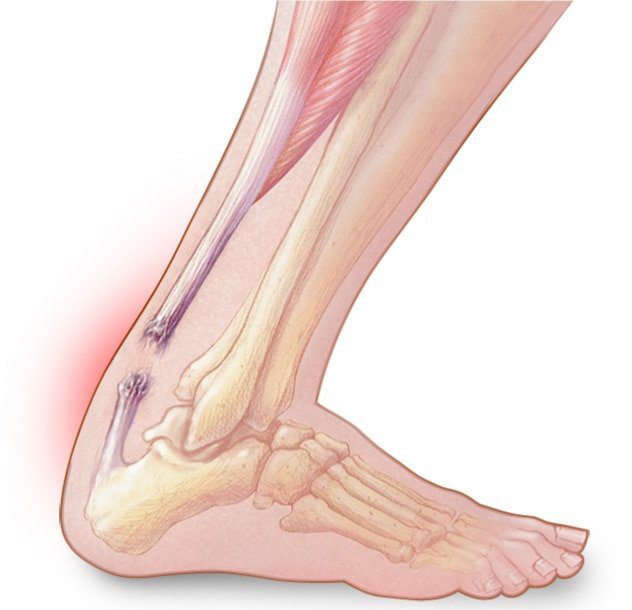

📌 El tendón de Aquiles

es el tendón más grueso y fuerte del cuerpo humano y desempeña un papel muy importante en la mayoría de los deportes y es particularmente vulnerable a la sobrecarga de la carrera y el salto reiterado.

⚽️ Las

roturas del tendón de Aquiles se dan con mayor frecuencia en deportes con balón que requieren cambios veloces de dirección y saltos rápidos y reactivos (p. ej. fútbol, tenis, pádel, etc).